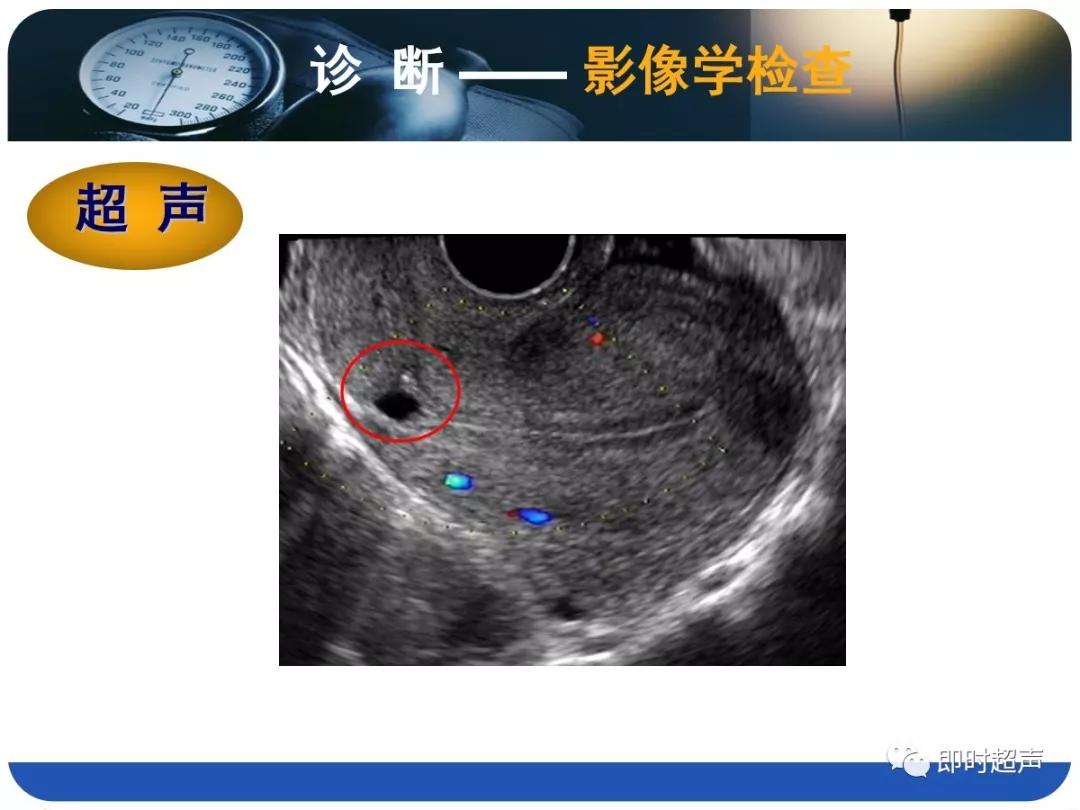

- 诊断主要依据病史(手术史)、临床表现(异常阴道流血)、检查结果(B超、HSG、宫腔镜等)综合判断。

- B超的特征性改变为:子宫下段或子宫峡部、宫颈管上段原剖宫产切口疤痕处肌层不连续,肌层内不规则液性暗区。